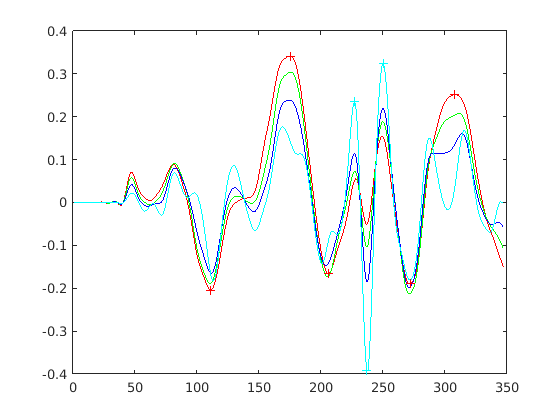

We find that , with values close to zero indicating locally flat regions, positive values indicating convexities, such as the pronasale (nose tip), and negative values indicating concavities, such as the nasion. Effectively this is a discrete approximation to finding the area within the facial profile that intersects with a disc of some predefined scale. The discrete sampling gives a high frequency quantisation noise on the signal and so we filter this with a 10th order low pass Butterworth filter.

The operator is very easily adapted to multiple scales, with smaller scales being straightforward subsamples of the disc points at larger scales. In this case, we reapply Eqn. 3 to the subsample and, as with the larger scale, apply a low pass filter. A useful property of the operator, in contrast to a standard curvature operator, is that its scale is easily tuned to the size of the features that one is interested in: we use a 20mm disc radius for most profile landmarks (nasion, pronasale, subnasale, chin concavity and pognion), except those around the lips (upper lip, lower lips, centre of lips), where we use the smallest scale, 5mm. Fig. 15 illustrates the disc operator’s output at four scales to illustrate its behaviour. For 5 of 8 facial profile landmarks, the strongest output is (usually) the largest scale. For the remaining three, the strongest output is the smallest scale.

|

|

The landmarking algorithm employed finds the nearest strong local extrema of the appropriate sign and at the appropriate scale. Our initial thought was to use a search from the largest to the smallest scale for all landmarks, We implemented this, but it often failed around the lip region, perhaps because the lower lip and upper lip localisations in the initial sparse model fit are very close to each other. Instead, we refine the pognion (chin), subnasale, pronasale (nose tip) and nasion at the largest operator scale. We then consider upper, centre and lower lips simultaneously by looking for a strong M-shaped disc operator signature at the smallest scale (5mm, cyan, in Fig. 15), between the subnasale and pognion. Finally, we find the chin cleft location as the strongest minimum between the lower lip and pognion.